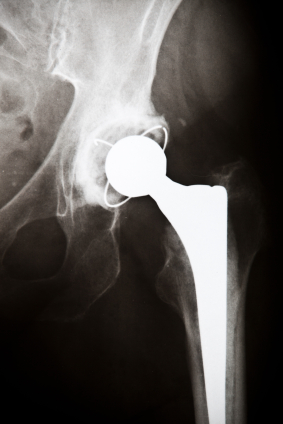

Biomet hip implant metallosis side effects lawsuit lawyersMetal on metal hip implant class action lawsuit lawyers can expect a new target as yet another metal hip replacement manufacturer admitted there might be risks for patients. British company Smith and Nephew says that its Birmingham metal on metal hip implant is at risk for failure.

Numerous recalls and warnings have been issued throughout the world. As yet, only the New Zealand equivalent of the FDA has warned surgeons not to use the Birmingham metal on metal hip implant in total hip replacement surgeries. Rather, many procedures are safer, including those using ceramic or plastic technologies as well as partial replacement options.

It may end up that DePuy metal on metal hip implant failure risks are simply due to the entire class of medical device. Rarely do so many companies exhibit the same type of problems leading to problems like DePuy, Stryker and Biomet hip implant metallosis side effects. All seem to either fracture or leach heavy metals into the body. These hip implant fracture risks can lead to organ punctures, severe pain, and reconstructive surgeries.